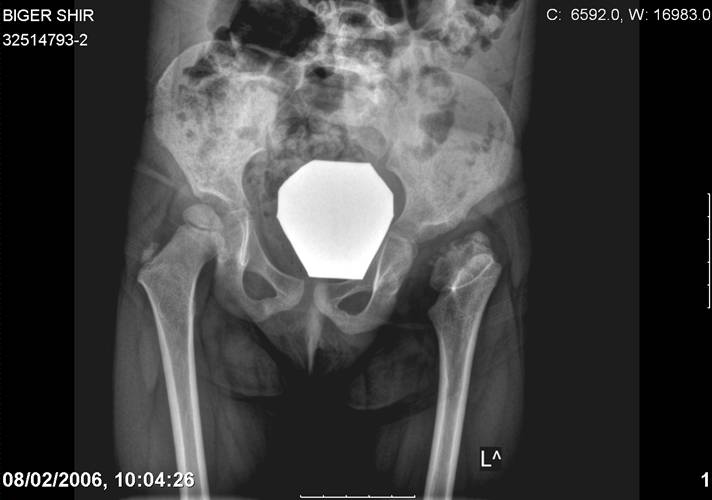

Здравствуйте, уважаемые коллеги.Обратилась девочка 6-ти лет из жалобами на боль в левом т/б суставе,хромоту Из анамнеза : ребенок лечился с рождения по поводу врожденного вывиха бедер. В возрасте 3- х лет в одной из клиник была выполнена остеотомия таза по Пембертону и варизирующая остеотомия бедра слева, справа - остеотомия таза по Солтеру и остеотомия бедра. Посоветуйте тактику лечения. С уважением Ihor

Smotritsya parshivo konechno(pseudoacetabulum,partial AVN), no v6 let ya by popytalsya ispravit chto moghno:shortening (ne boyatsya ubrat bolshoi fragment),derotation(30 gradusov ne bolshe)+pelvic osteotomy in true acetabuluam area.Obyazatelno takghe open reduction with wide capsular exposure.